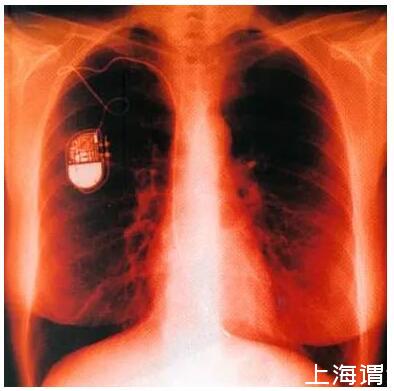

按應用形式分類有:植入式傳感器、暫時植入體腔(或切口)式傳感器、體外傳感器、用于外部設備的傳感器

植入式傳感器